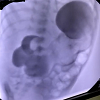

Case presentation: Our case is a neonate with an intraluminal pyloric duplication cyst who presented with recurrent vomiting. The radiological evaluation suggested a duplication cyst medial to the second part of the duodenum towards the stomach’s lesser curvature with features of gastric outlet obstruction. Intraoperatively, a cystic mass of 1 x 2 cm intraluminally was found on opening the pylorus which was excised and pyloroplasty was done. Postoperatively the baby was discharged in a stable condition.